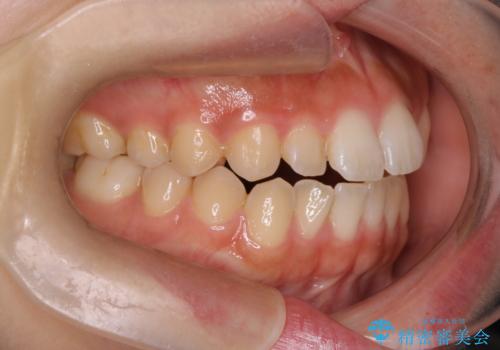

【インビザライン】がたつきをマウスピースできれいにしたい

- 20代女性

- 前歯の叢生を主訴に来院されました。非抜歯でインビザラインで治療をしました。

叢生はIPRをし、並べました。この患者様はオープンバイトだったため歯を並べる過程でかみ合わせも治しました。